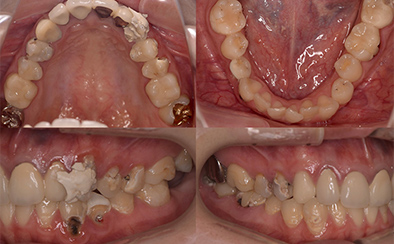

治療前

治療後

なるべく歯を残して、歯の神経も可能な限り保存し残していく方向で治療方法を検討しました。むし歯が大きく神経が侵されている歯は、抜髄を行い、精密根管治療の後にセラミックスクラウンを被せる治療方法を策定しました。患者さんのご希望と了解を得て治療を開始しました。

むし歯治療では、丁寧にむし歯だけを除去して健全な歯質だけを残します。名取歯科医院では、ラバーダムとマイクロスコープの使用が標準です。歯の根と神経の治療(根管治療)も行っていきます。

ラバーダムとはゴム製のシートで、治療する歯だけを露出させるように丁寧に切り取り、お口に装着します。唾液の中には天文学的な数の細菌が存在するため、一度治療した歯が再び悪化して再治療とならないためには、ラバーダムを装着し唾液や細菌に触れないように防湿を施した環境で治療することが何よりも大切で、歯科治療の基本です。歯の根元の黒い部分は膿の溜まった袋です。

むし歯が進行することで歯の神経まで細菌に侵されてしまった場合、昭和型の歯科治療では歯を抜いてしまう抜歯が当たり前でした。しかし、歯を抜いてしまうことで歯並びの乱れなど、ほかの歯への大きな影響があります。そこで自分の歯をできるだけ残すことを考えた「根管治療」や「保存治療」が選択されるようになってきました。

治療後の写真です。きちんと歯の根の治療(根管治療)を施すことで膿の袋も消失します。

歯ぐき(歯肉)の治療も大切です。歯ぐきを健康的な状態に治療していくことで、お口全体を審美的に優れた美しい状態に改善できます。このように歯ぐき(歯肉)の治療を行うことで、炎症を抑え、健康な状態をつくることができます。歯ぐきのコンディションを回復させると同時に、仮歯を入れます。しかしこれは治療中の隙間を埋めたり見た目を取り繕う「仮歯」とは異なります。プロビジョナルレストレーションと言い、最終的な歯(本歯)と同じ形体をもつ歯で、治療した歯や周囲の歯、反対側の歯、歯ぐきなどお口全体の回復と調和を整える大切な治療プロセスです。もちろんこの期間に仮歯での噛み合わせ、咀嚼や嚥下、または発音や発語など機能的な回復に不具合がないか、顎関節への影響や負担がないか検証する期間でもあります。

仮歯で機能回復の確認を行い、そしてさらに微調整を行います。機能的・審美的に改善を確認できた仮歯の形態を元にセラミックスクラウンを作製します。熟練した歯科技工士によるセラミックス制作を行い、装着後に最終的な微調整(咬合調整)を施し、むし歯治療、歯の根の神経治療(根管治療)、白いセラミックスによる修復治療のすべてが終了しました。

| 費用 | ジルコニアセラミック24本:5,280,000円 根管治療(小臼歯5本):770,000円 根管治療(前歯6本):792,000円 合計:6,842,000円 |